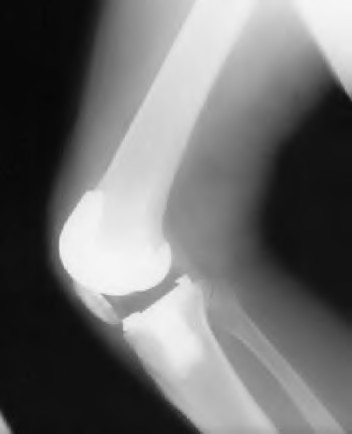

A 75-year-old female sustains a fall 5 years after a cementless THA. Radiographs show a periprosthetic femur fracture occurring around the stem tip. Intraoperative assessment reveals the stem remains firmly fixed in the metaphysis, and the proximal bone stock is adequate. According to the Vancouver classification, what is the fracture type and the standard recommended treatment?